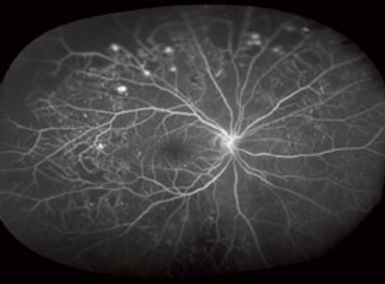

Diabetic Retinopathy: Causes and Treatment

Diabetic retinopathy is a diabetes-related eye condition that damages the blood vessels in the retina. It can occur in individuals with both Type 1 and Type 2 diabetes. Causes of diabetic retinopathy include:

Treatment for diabetic retinopathy may involve laser photocoagulation, anti-VEGF injections (such as bevacizumab, ranibizumab, or aflibercept), or vitrectomy. Early detection and management are crucial in preventing vision loss.